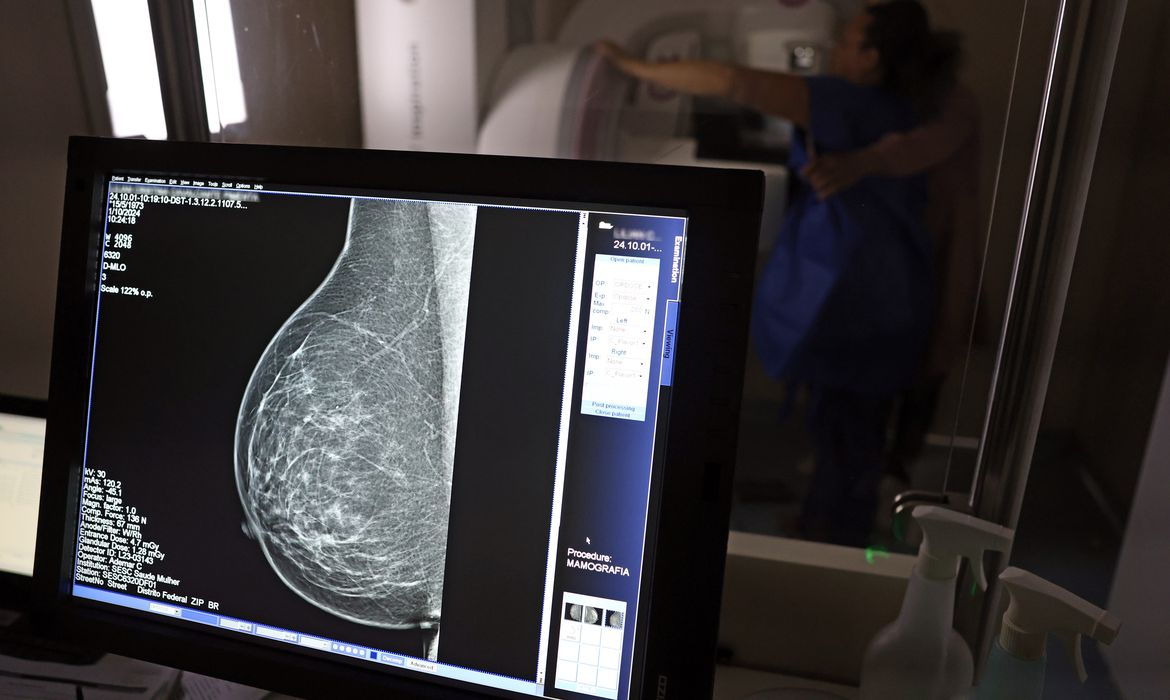

Foto: © José Cruz/Agência Brasil medida também busca incentivar a prevenção e o diagnóstico precoce

medida também busca incentivar a prevenção e o diagnóstico precoce

A medida também busca incentivar a prevenção e o diagnóstico precoce, considerados fundamentais para aumentar as chances de tratamento e cura. Especialistas apontam que muitas doenças, como os cânceres de mama, próstata e colo do útero, têm maiores índices de sucesso quando identificadas nos estágios iniciais. Com a nova exigência, a expectativa é que mais trabalhadores tenham acesso à informação e utilizem o direito ao afastamento para cuidar da saúde de forma preventiva, sem prejuízo financeiro.